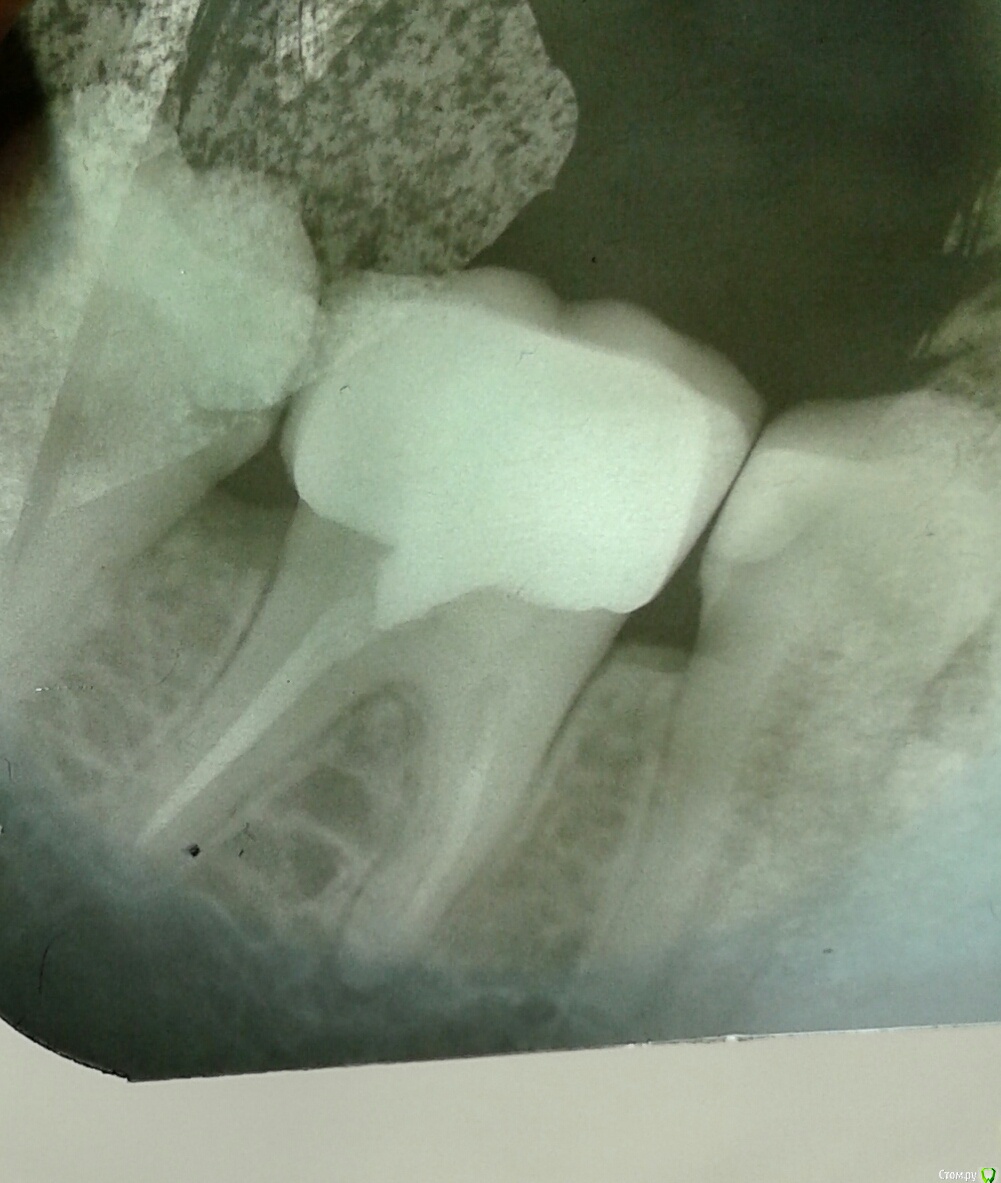

Инна2106 Опубликовано 27 июля, 2018 Автор Поделиться Опубликовано 27 июля, 2018 Еще снимок Ссылка на комментарий

kramer Опубликовано 27 июля, 2018 Поделиться Опубликовано 27 июля, 2018 (изменено) Да банально пульпит нижней семерки. Там кариес под пломбой, видно же. Изменено 27 июля, 2018 пользователем kramer 1 Ссылка на комментарий

Инна2106 Опубликовано 27 июля, 2018 Автор Поделиться Опубликовано 27 июля, 2018 На снимке не могу понять, в семерке как не видно одного корня зуба (я про что в 6-ке и 8ке их два, а в 7-ке один и второй как пятно). Что это означает?Как и сказано было выше, я насчитал с этой стороны 5 зубов, которые могут давать такую симптоматику, но из них 7ка наиболее вероятно. Ссылка на комментарий

kramer Опубликовано 27 июля, 2018 Поделиться Опубликовано 27 июля, 2018 На снимке не могу понять, в семерке как не видно одного корня зуба (я про что в 6-ке и 8ке их два, а в 7-ке один и второй как пятно). Что это означает?Сорри, не понял ваш вопрос. Все видно, 2 корня. Ссылка на комментарий

Инна2106 Опубликовано 27 июля, 2018 Автор Поделиться Опубликовано 27 июля, 2018 (изменено) когда смотришь на снимок зубов два корня и два канала, на 6 и 8-м зубах это четко видно в 7-м один видно второй не ясно где, визуально. Эта трещина на снимке под пломбой и есть кариес?Сорри, не понял ваш вопрос. Все видно, 2 корня. Изменено 27 июля, 2018 пользователем Инна2106 Ссылка на комментарий

kramer Опубликовано 27 июля, 2018 Поделиться Опубликовано 27 июля, 2018 (изменено) когда смотришь на снимок зубов два корня и два канала, на 6 и 8-м зубах это четко видно в 7-м один видно второй не ясно где, визуально. Эта трещина на снимке под пломбой и есть кариес? Я не знаю, куда вы смотрите, но мне видно все Трещина на снимке не может быть определена. А вот кариес видно. Он прям под пломбой. Изменено 27 июля, 2018 пользователем kramer Ссылка на комментарий